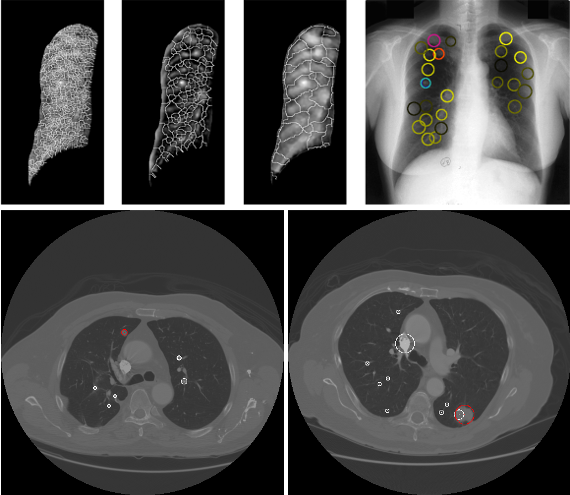

Com o projeto Lung CAD, pretendemos criar um sistema de diagnóstico auxiliado por computador que será útil na deteção de lesões pulmonares, tais como pequenos nódulos, ou nódulos não sólidos como opacidades em vidro despolido (ground glass opacities).

O objetivo do Laboratório de Imagem Médica consiste em conceber e implementar sistemas CAD que automaticamente detetam e geram provas para que os radiologistas possam otimizar um diagnóstico precoce e assim maximizar os tratamentos médicos. É dado especial enfoque à deteção de nódulos subtis e nódulos não sólidos tais como opacidades em vidro despolido.